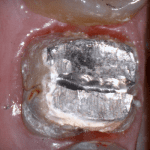

In this clinical video we demonstrate how to scan a molar preparation for the replacement of a crown with recurrent decay and open margins. The molar was root canal treated and the tissue was inflamed. the preparation was imaged and a temporary was fabricated to allow the tissue to heal properly.

The main point of this video is to show how to capture the contacts of the adjacent teeth and the deep marings